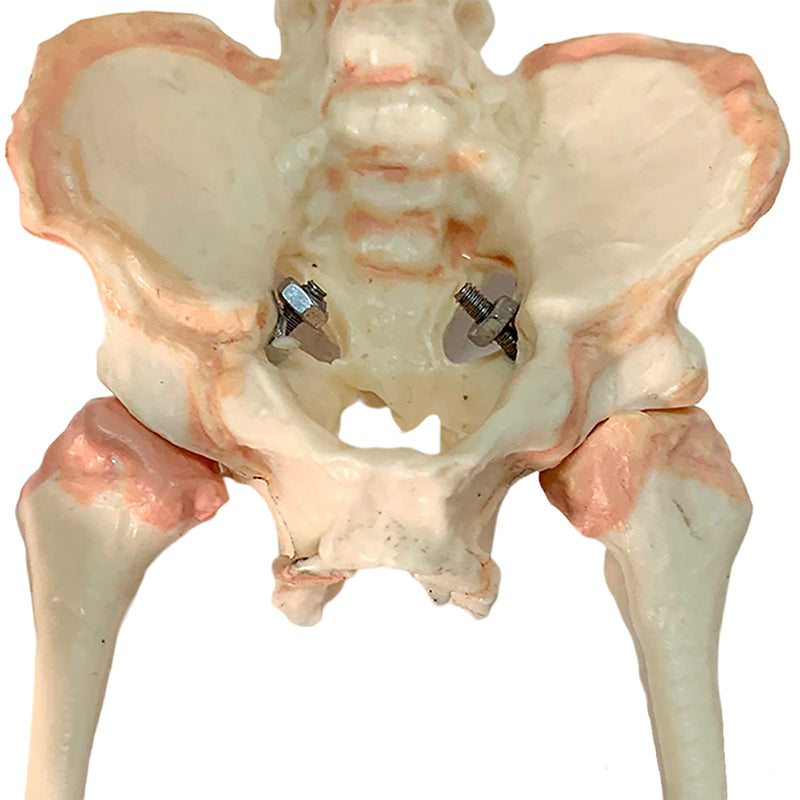

Fetal Skeleton

Life-size model with detachable parts that presents the bone morphology of the fetus. The model reflects the initial state of the bones of a 10 month old fetus and can be removed from the base for detailed examination, the stand unscrews and separates from the base for easy storage when not in use. Accompanying an interactive 3D anatomical model with augmented reality is a great tool to encourage learning and support. This platform allows students to engage in comparative analysis of anatomical models as they compare and contrast the structure of individual organs. This initiative also provides a platform for continuing education, providing opportunities for all students to increase their knowledge of anatomy, physiology and pathophysiology.

Fetal Skeleton

Life-size model with detachable parts that presents the bone morphology of the fetus. The model reflects the initial state of the bones of a 10 month old fetus and can be removed from the base for detailed examination, the stand unscrews and separates from the base for easy storage when not in use. Accompanying an interactive 3D anatomical model with augmented reality is a great tool to encourage learning and support. This platform allows students to engage in comparative analysis of anatomical models as they compare and contrast the structure of individual organs. This initiative also provides a platform for continuing education, providing opportunities for all students to increase their knowledge of anatomy, physiology and pathophysiology.